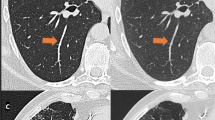

CT images of a cadaveric lung with diffuse panbronchiolitis. Whole and zoomed CT images of AD-CT (a, b, and c), U-HRCTSHR (d, e, and f), and U-HRCTSHR-VOL (g, h, and i). Tiny (2-mm-diameter) nodules show ill-defined margins and unclear internal structure (b). Dark band artifacts (arrowheads) can be seen (c). Tiny nodules show well-defined margins and clear internal structure (air bronchiologram) (e and h). There are almost no dark band artifacts (f and i). Both U-HRCTSHR (d) and U-HRCTSHR-VOL (g) produced significantly better overall image quality than AD-CT (a). AD-CT: area detector CT. U-HRCTSHR: ultra-high-resolution CT with super-high-resolution mode U-HRCTSHR-VOL: ultra-high-resolution CT with volume mode